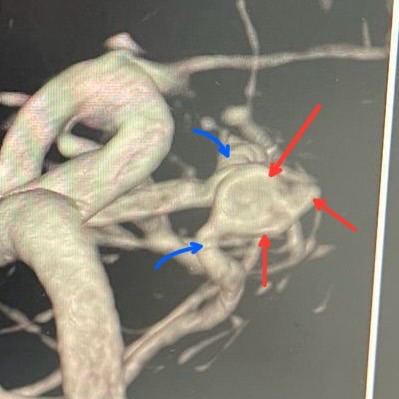

في الصور اللي قدامكم، أنا مشاور على التمدد الشرياني بالأسهم الحمراء 🔴.

والصور دي معمولة بتقنية 3D rotation اللي بتوفرها أجهزة القسطرة الحديثة، ودي تقنية بتورّي لنا التمدد من كل الزوايا، علشان نفهم شكله بدقة، ونعرف فين الرقبة، وفين مكان خروج الشرايين منه.

هتلاقوا كمان سهمين زرق 🔵… دول بيوضحوا الشريانين الطبيعيين اللي طالعين جنب التمدد مباشرة. التمدد ده طالع من منطقة تفريعية بين الشريانين، وده معناه إن أي خطأ بسيط ممكن يؤدي إلى قفل أحد الشرايين… وممكن ده يسبب جلطة في المخ.